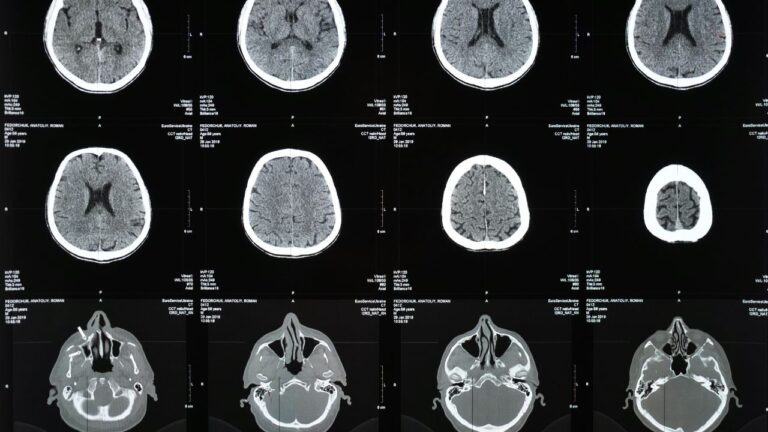

Brain Imaging in Traumatic Brain Injury (TBI) Research

A traumatic brain injury rarely announces its full damage on day one. The CT scan might look “clean.” The patient might even walk out ...

Neuroimaging Tools Used in Stroke Diagnosis and Recovery

When a stroke hits, time doesn’t just matter—it is the diagnosis. Every minute, nearly two million neurons die. In that frantic window between symptom ...